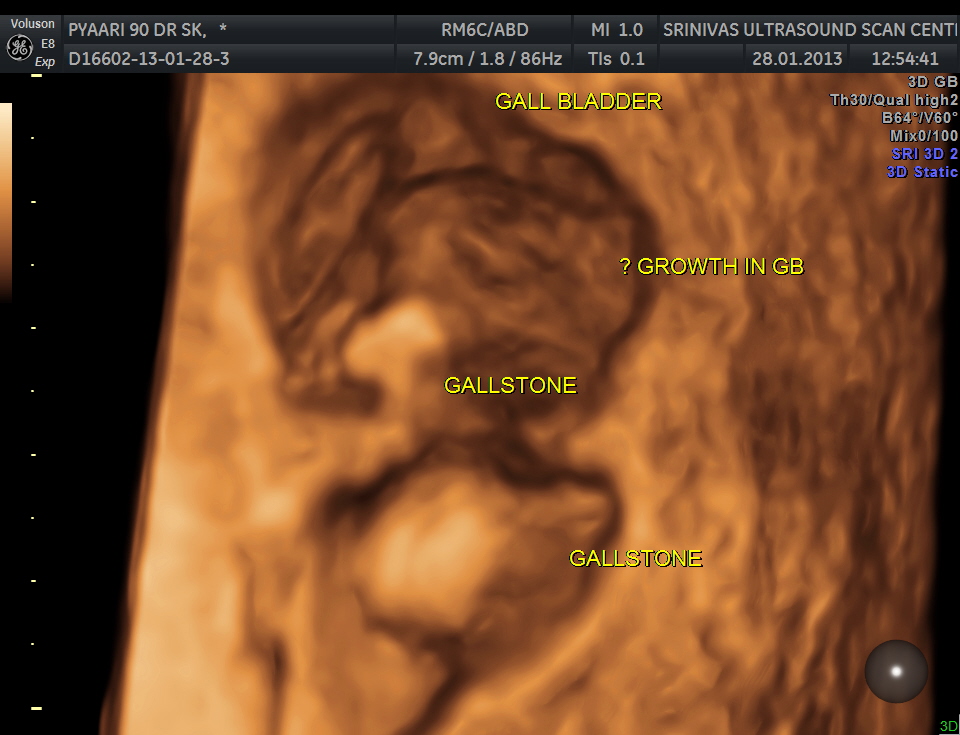

3 D view of the same.

The fundus shows irregular growth and a gallstone.